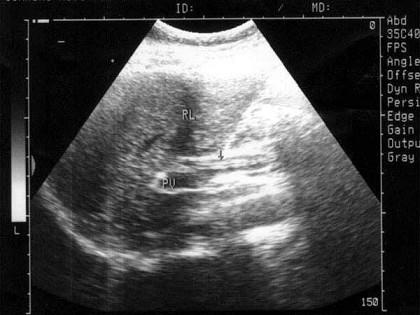

问题 患者女33岁,右上腹剧痛5小时,体检:右上腹压痛及叩击痛(弱阳性),B超检查如图所示,根据超声声像图,诊断为?(?)

选项 A.胆总管结石 B.胆总管引流管回声 C.胆总管蛔虫 D.胆总管胆泥淤积 E.胆总管癌

答案 C